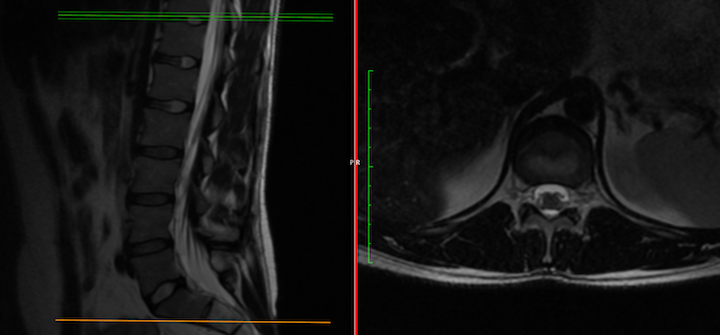

Does this patient have obvious arachnoiditis?

Pt. has had four MR of the the thoracic spine, all yielding an interpretation of visible soft tissue masses at T8 & T11. Pt. also has degenerative changes, moderate foramenal stenosis at L5/S1, L4/L5...and the last neurological rad providing interpretation of lumbar MR, noted pt has arachnoiditis, with "empty sac sign"...moderate to severe.

Given the limited treatment options available for arachnoiditis or the adhesive version, I am curious as to what others thoughts are on this Pts. imaging.... any eyes would be appreciated.